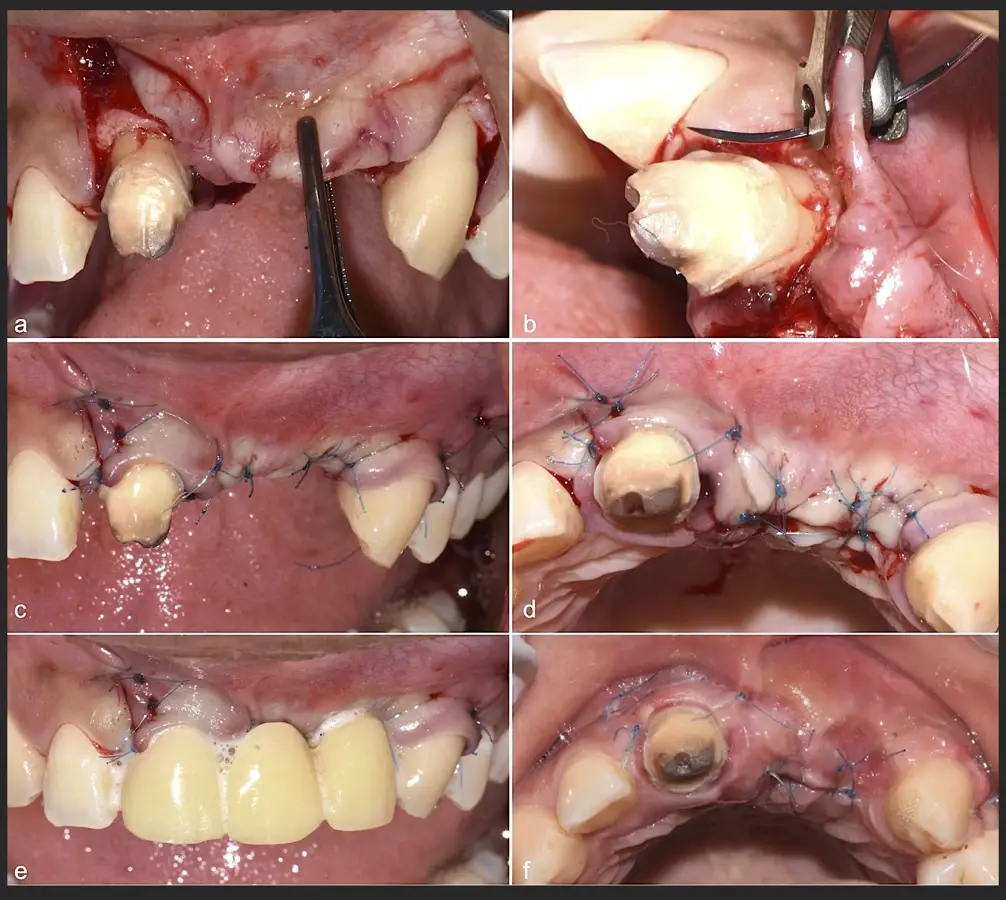

Figura 45. Afrontamiento de colgajo y sutura (a - e). Control a los 7 días postquirúrgico (f).

Figura 46. Control a los 10 días post cirugía.

Conclusión

Estos dos casos clínicos evidencian las ventajas de la cirugía piezoeléctrica en procedimientos de terapia ósea regenerativa como reconstrucción de reborde con injertos en bloque o reconstrucción de lechos para implantes dentales.

Serie Especial: Piezocirugía

Haga clic aquí para ver el resumen de los 11 artículos.

La serie de artículos sobre Piezocirugía está basada en el libro de José Carlos Rosas y colaboradores sobre esta tecnología.

El libro, escrito con Jerson Palomino Zorrilla, Karla Díaz Cavero y María Eugenia Guerrero Acevedo, de la Universidad Privada San Juan Bautista, en Lima (Perú), ofrece la evidencia científica más actual para respaldar el valor clínico de diversos procedimientos con piezoeléctrico, cuya utilidad práctica en el consultorio demuestra mediante la publicación de numerosos casos clínicos.

El libro "Cirugía piezoeléctrica. Generalidades y aplicaciones clínicas" explica los fundamentos de esta tecnología y muestra su utilidad práctica en el consultorio mediante casos clínicos.